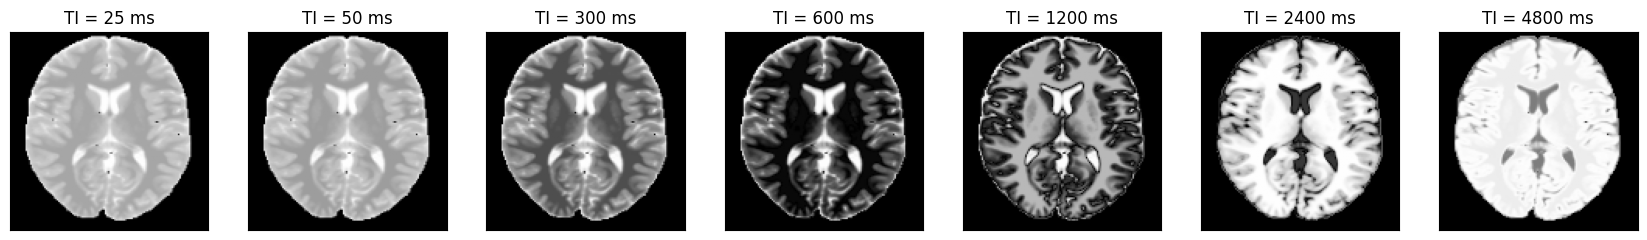

We can now plot the images at different inversion times.

idat = idata.data.abs().numpy().squeeze()

fig, ax = plt.subplots(1, idat.shape[0], figsize=(3 * idata.shape[0], 3))

for i in range(idat.shape[0]):

ax[i].imshow(idat[i, :, :], cmap='gray')

ax[i].set_title(f'TI = {int(idata.header.ti[i] * 1000)} ms')

ax[i].set_xticks([])

ax[i].set_yticks([])